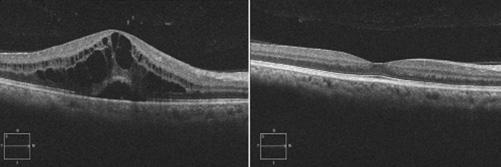

Trabéculotomie autonome et viscodilatation du canal de Schlemm et des canaux collecteurs dans le glaucome à angle ouvert à l’aide du système chirurgical OMNI : résultats à 24 mois

Objectif : Pression intraoculaire (PIO), résultats de la médication à 24 mois après trabéculotomie/viscodilatation à l’aide du système chirurgical OMNI® en tant que procédure autonome dans le glaucome à angle ouvert (GAO) léger à modéré non contrôlé médicalement110

Conception : Analyse rétrospective. Les données relatives à la PIO et aux médicaments ont été recueillies avant l’opération et pendant 24 mois. Les données de sécurité comprenaient les événements indésirables et la nécessité d’une intervention chirurgicale supplémentaire.

Méthodes : Élimination des médicaments avant l’opération. Tonométrie de Goldmann. Nombre de médicaments et d’événements indésirables à chaque point dans le temps.

Résultats primaires : Changements dans la PIO et les médicaments. Des tests t bilatéraux par paires comparent les valeurs à chaque suivi avec la ligne de base, signification p = 0,05. Résultats secondaires : proportion d’yeux avec une réduction de la PIO de ≥ 20 %, avec moins de médicaments et sans médicaments à chaque point dans le temps.

Résultats : Cette analyse a porté sur les données de 38 yeux de 27 sujets. La PIO initiale moyenne (écart-type) était de 24,6 (3,0) mm Hg et, après 24 mois, elle variait de 12,6 à 14,9 mm Hg (p < 0,0001), ce qui représente des réductions de 10,0 à 12,0 mm Hg. La moyenne des médicaments était de 1,9 (au départ) et, au cours des 24 mois, elle a varié de 0,0 à 0,5 (réduction de 70,6 à 100 %) (p < 0,0001). Au 24e mois, la PIO moyenne était de 14,9 mm Hg (-10,0 mm Hg), et 100 % des yeux avaient obtenu une réduction de la PIO de > 20 % par rapport à la valeur initiale; la consommation moyenne de médicaments était de 0,5 (-1,4 médicaments, p < 0,0001), 84,6 % des yeux utilisaient > 1 médicament de moins, et 57,7 % n’utilisaient aucun médicament. L’événement indésirable le plus fréquent était l’hyphème peropératoire (44,7 %), qui s’est résolu spontanément. Il y a eu deux procédures secondaires pour le contrôle de la PIO.

Conclusion : Le système chirurgical OMNI permet des réductions cliniquement pertinentes et statistiquement significatives de la PIO et des médicaments avec un excellent profil de sécurité et devrait être envisagé dans les yeux phaques ou pseudophaques avec un GAO léger à modéré nécessitant une réduction de la PIO ou des médicaments, ou les deux.